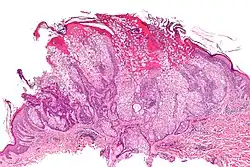

| Micrograph of a sebaceous adenoma. H&E stain. | |

Sebaceous adenomais a type of adenoma, characterized by a slow-growing tumor usually presenting as a pink, flesh-coloured, or yellow papule or nodule.[1]: 662 [2]